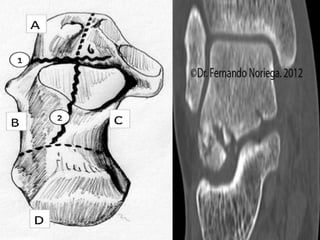

CLASIFICACIÓN AO/MÜLLER DE LAS

FRACTURAS DE LOS HUESOS LARGOS

 Se basa en 3 segmentos: Región

trocantérica, el cuello y la cabeza femoral.

 Fractura intracapsular: Dependiendo del

grado de desplazamiento puede

correlacionar un riesgo de complicación.

 Fractura extracapsular: Es mejor clasificarlas

en estables e inestables.

Evaluamos la

estabilidad de acuerdo

al grado de

conminución.

Afectación del

calcar femoral